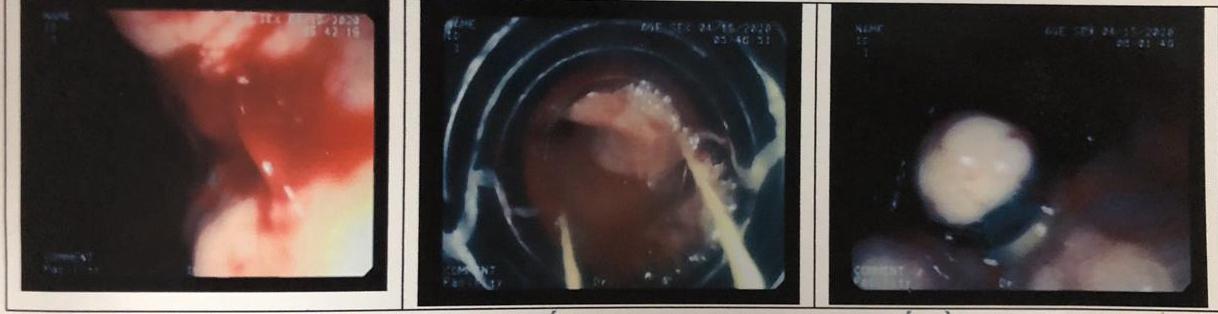

Hình ảnh nội soi từ trái sang: Tia máu tại vị trí vỡ búi tĩnh mạch; Tiếp cận búi vỡ; Thắt cầm máu búi tĩnh mạch vỡ

Khi huyết động của bệnh nhân đã ổn định, ekip tiến hành nội soi thăm dò và đánh giá khả năng can thiệp. Đưa ống soi vào thực quản, dạ dày phát hiện bên trong có rất nhiều máu đỏ lẫn máu cục lên đến gần 1000 ml. Thực quản có các tĩnh mạch giãn căng, ngoằn ngoèo nổi cao lên khỏi bề mặt niêm mạc, gần tâm vị có búi tĩnh mạch bị giãn vỡ, máu đang phun thành tia.

ThS.BS Nguyễn Hà Thường – Trưởng khoa Nội soi – Thăm dò chức năng nhận định, nếu bệnh nhân không được cấp cứu và xử lý kịp thời sẽ có nguy cơ tử vong cao do búi máu phun thành tia gây chảy máu ồ ạt, hơn nữa trên nền bệnh nhân bị ung thư gan, xơ gan, suy tế bào gan dẫn đến rối loạn nghiêm trọng chức năng đông máu, khiến cho tình trạng mất máu trầm trọng hơn, không thể tự cầm. Các bác sĩ đã quyết định sử dụng thủ thuật nội soi can thiệp thắt búi tĩnh mạch thực quản bị giãn vỡ bằng vòng cao su, cầm máu thành công cho bệnh nhân.